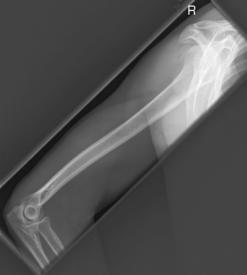

(Midhumerus and Distal Humerus)

For proximal humerus, see transthoracic lateral or scapular Y.

(External and Internal Rotation)

Warning: Do not attempt if fracture or dislocation is suspected.